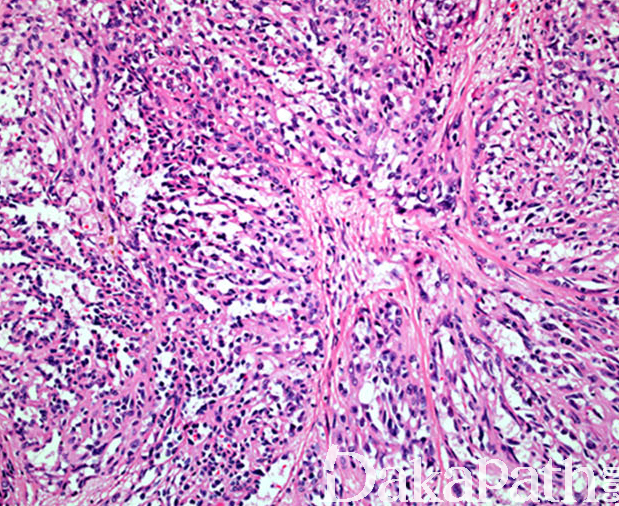

- 镜下良性血管瘤、中间型血管内皮瘤和血管肉瘤成分混合组成,三者比例多少不等;

- 良性血管瘤成分可表现为梭形细胞血管瘤、动静脉畸形和局限性淋巴管瘤;

- 中间型血管内皮瘤成分包括上皮样血管内皮瘤和网状血管内皮瘤;

- 血管肉瘤成分常由分支状或交通状的肿瘤性血管组成,内衬的内皮细胞有一定的异型性,可见少量核分裂像,罕见坏死;

- 部分肿瘤内可见大量空泡状的内皮细胞,呈假脂肪母细胞形态。